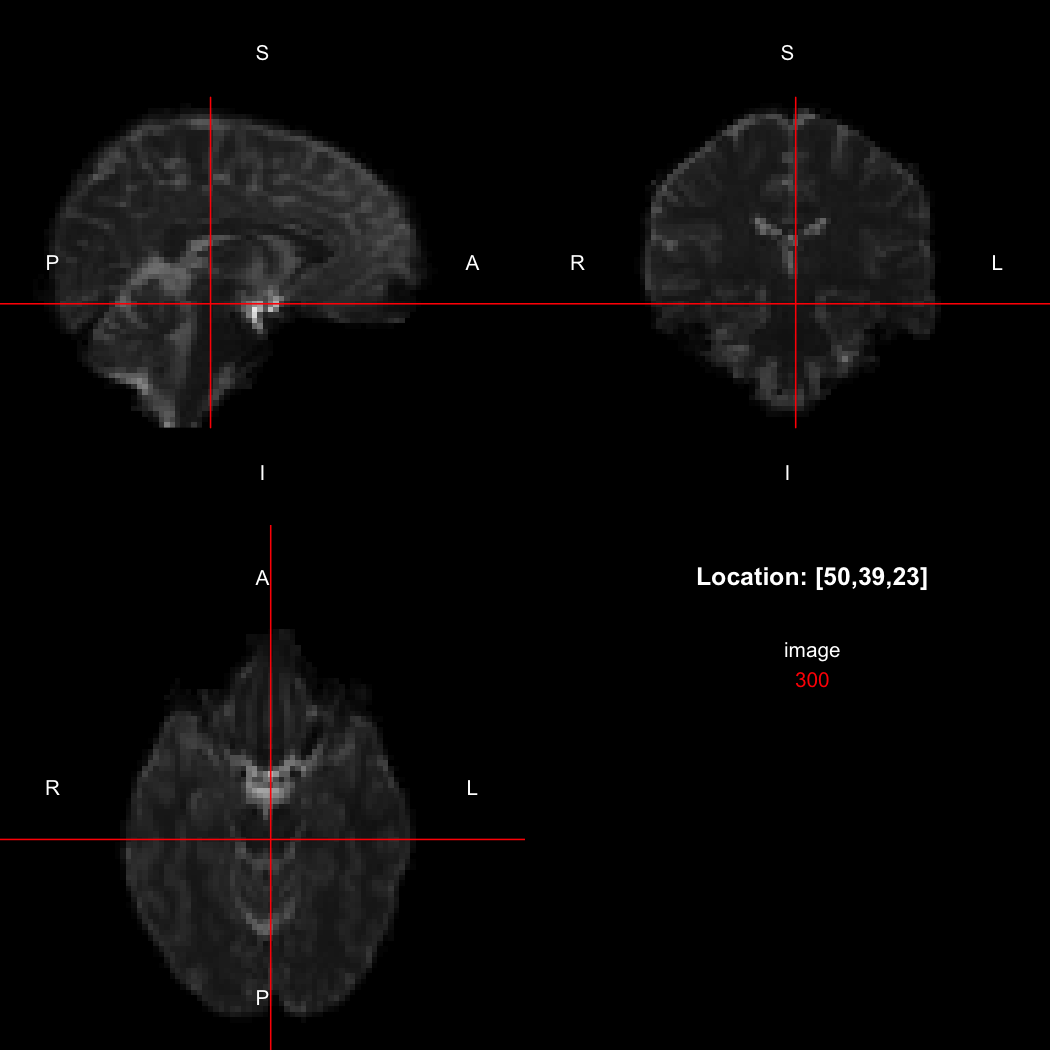

The package contains a basic image viewer, which can be used interactively or noninteractively to examine 2D or 3D images.

view(image)

By default, the viewer shows labels indicating image orientation, crosshairs pinpointing

the currently selected location, the numerical indices of the current

location, and the value of the image at that location. Options allow

each of these to be turned off, for the content of the bottom-right

panel to be customised entirely, for the colour scale to be changed, and

for additional images to be layered on top of the base image. See

?view for details.

## [1] "LAS"So, here, “LAS” means that the positive x-axis points left, the positive y-axis anterior and the positive z-axis superior. This is the so-called “radiological” orientation convention, and can be requested when viewing images for those who are used to it:

view(image, radiological=TRUE)

Notice the left (L) and right (R) labels, relative to the view shown

above. Setting the radiologicalView option to

TRUE will make this the default for all future views.